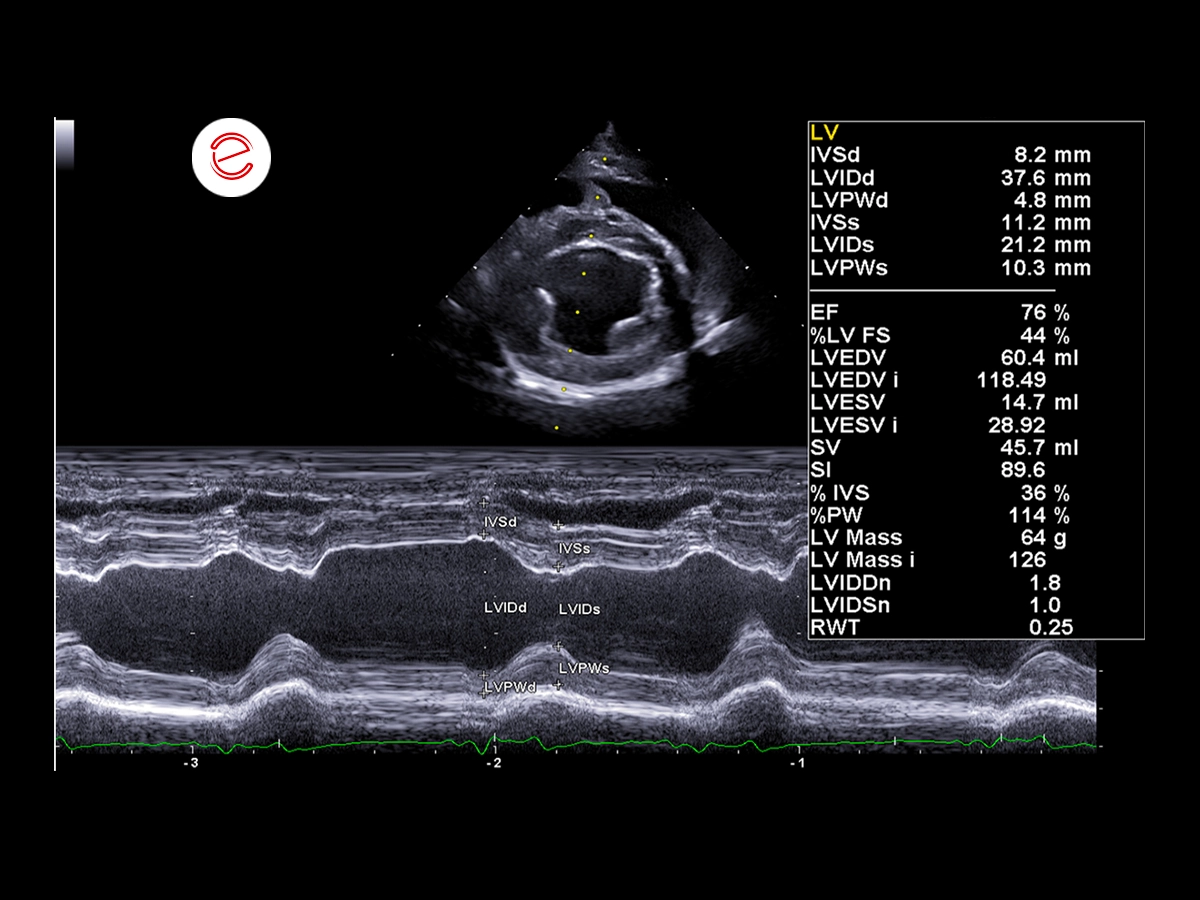

M-Mode measurements revealed left ventricular enlargement, as evidenced by an increased LVIDDn (1.8) value exceeding the normal reference range (<1.7).